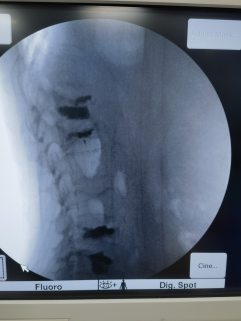

年龄70岁以上的老年人自身的各项机能处在低位运行状态,心、肝、肾功能也明显下降大部分伴有多种基础性疾病,如果遇上外伤不及时治疗,会产生许多并发症,很可能成为老年人生命的终点。 老年人常见的外伤:1, 椎体压缩性骨折2, 股骨颈骨折 一个医生的职责所在;就是开辟绿色通道,尽早,尽快解除外伤给老年人带来的痛苦。 2024年6月24日周一下午1:00准时打开诊室大门,见一位男性患者坐在轮椅上被推进诊室,患者进门第一句话;“童医生,你救救我,” 我习惯性看了一眼电脑挂号记录,男。78岁,我再定睛一看,患者是一位认识十多年的老熟人,身材魁伟的老朱,老朱平时说话声音洪亮,也是一个非常好心和热心肠人,时常无私的帮助他人,目前自己还在自家的模具工作室工作,平时根本看不出已经是78岁高龄。我观察到患者脸上流露出非常痛苦的表情,原本魁梧的身体卷缩在轮椅上一动也不敢动,。我立刻问到;“老朱,你怎么不好,哪里疼痛?”,老朱回答;“我摔了一跤,现在腰部非常疼痛,身体轻微移动疼痛会更加厉害,一动我的腰就像断裂一样,”我追问到;“你是上腰痛还是下腰痛,是否有下肢放射性疼痛,”老朱回答说;“整个腰部疼痛,双侧屁股疼痛,没有双侧下肢放射性疼痛,腰部疼痛好像有两根带子从背部向两侧腹部放射”通过简单的询问,我抓住病史的关键点:1, 外伤,2, 束带状腰痛,3, 双侧环跳疼痛,;我初步判断外伤造成患者上腰椎压缩性骨折和下腰部椎间盘纤维环撕裂,软组织损伤。当今诊断脊柱外伤的首选检查方法,是腰椎MR检查。在征得患者同意后,为了尽快明确诊断,我立即电话联系放射科,开通绿色通道,让患者插队做腰椎MR检查。半个小时后,腰椎MR检查结束,果然和我初步诊断完全吻合;1,第二腰椎压缩性骨折2,下腰部椎间盘纤维环撕裂伴软组织损伤。我如实把诊断意见告诉患者,提出我的治疗方案;抓住主要,暂缓次要。治疗分二步走;1, 先治疗腰椎压缩性骨折,然后回家绝对卧床休息二周,如果腰痛症状明显缓解就继续卧床休息,2, 如果腰痛症状缓解不明显再用童氏精准无创介入治疗下腰部椎间盘纤维环撕裂,软组织水肿。我告诉患者目前国内治疗腰椎压缩性骨折的三种治疗方法;1, 手术治疗+打钢钉2, 保守治疗;回家绝对卧床休息三个月3, 微创介入治疗-患者明智的选择第3种微创介入治疗(PVP),这是当今国内外治疗椎体压缩性骨折的首选治疗方法。我们开展的PVP微创介入治疗方法是国内独家CT+C臂X光机3维引导技术,1998年开展自今零风险。我问患者为什么不选择1或2,患者说;保守治疗,我忍受不了三个月腰部剧烈的疼痛,而且年纪大了还不一定养的好。手术治疗,我更不考虑,手术治疗必须过三关,麻醉关,手术关,康复关,而且需要打钢钉,我年纪大了椎体骨质已经疏松了,钢钉打进骨质疏松的椎体里还有用吗?让我更惊呀的是患者说不手术的真正的理由;他有一个朋友和他年龄差不多,几年前患了腰椎间盘突出,为了得到更好的治疗,他的朋友通过多方打听,并且找门路,通关系挂上了平时根本预约不上的上海某个三甲医院骨科主任,博士生导师的门诊号,因为患者有人介绍,主任医师也尽快的将患者收入医院手术治疗,出院结账花了十几万,意想不到的是术后不到三个月患者去世了。我听后无语,心里默默为逝者默哀我们开展的PVP微创介入治疗方法是国内独家利用CT + 移动C臂X光机3维可视引导技术,治疗过程中患者无疼痛感,安全性极高,1998年开展自今零风险,无并发症。CT + 移动C臂X光机3维可视引导技术明显优于国内普遍使用DSA或者移动C臂X光机平面透视引导技术,平面透视引导穿刺角度难以掌控,穿刺角度不足,往往需要双侧椎弓根二次穿刺,穿刺次数每增加一次,出现医疗风险机率增大一倍。平面透视引导出现过骨水泥滲漏到椎管内造成患者下肢瘫痪,平面透视引导出现过穿刺针穿破椎体前方造成腹主动脉破裂,腹主动脉旁血肿的人为的次生损伤。老朱住院做了椎体压缩性(PVP),治疗,术后二周上腰痛有所缓解,下腰痛缓解不明显,征得患者同意,采取童氏精准无创介入治疗下腰痛;椎间盘纤维环撕裂和腰部软组织水肿,二个疗程后,患者打电话来说;童医师,非常感谢你的治疗,帮助我这么快的恢复健康,我现在又可以上班了。我对他说;也要感谢你,对我的信任和支持。任何疾病的治疗需要医患双方的信任和支持,在我32年的脊柱介入行医经历中,我也遇到不少前来面诊的腰椎间盘突出和腰椎骨折患者,在明确诊断后,我也尽力、详细为患者和家属介绍,解释患者的病情严重程度和我的治疗方法,但是这些患者还是拂袖而去,有的可能选择放弃治疗、有的可能选择手术治疗。对于一种疾病会有多种治疗方法,医师无权干涉患者的选择权,选择权在患者和家属这里,人各有志,不能勉强有一句话说的好;“人生就是选择,然后承受相应的后果。”患者在做出选择任何一种治疗方法之前,尽量对这个疾病和治疗方法多做了解,避免踩坑。让你的亲人,尤其患有多种基础疾病的老年患者尽快从痛苦中脱离出来,远离死亡的危险。有一句忠告;要选择有责任心,仁心,尤其是要有同情心的医师,不一定要迷信那些头戴各种光环的专家,一个人的精力和能力是有限的,当你把大量的时间和精力在放在外出开会,讲课,应酬上,那么放在临床专业研究上的精力和时间、与患者沟通交流的机会就所剩无几。作为一个称职的医师可以救死扶伤,挽救生命,解除患者痛苦。作为一个不称职的医师可能就是一位具有行医资格证书的职业杀手。